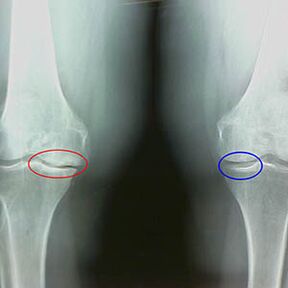

La determinación del grado de artrosis ocurre mediante rayos xrevelando la participación en el proceso patológico de las estructuras óseas. Su cambio indica que el sistema muscular ha estado en un desequilibrio durante 5-10 años. Como regla, la gente Durante varios años experimentan dolores dolores.

En la primera etapa de la artrosis, que se detecta por accidente, se produce un ligero aumento en las espuelas óseas. Los crecimiento aparecen en lugares de la mayor inestabilidad de la articulación. Por lo general, los pacientes rara vez experimentan dolor o incomodidad durante el movimiento.

La segunda etapa de la artrosis se considera fácil. La radiografía revela espuelas óseas significativas, pero el cartílago no se ve afectado. La cantidad de líquido sinovial se reduce, pero los síntomas de dolor aparecen después de una larga caminata y carrera, rigidez en la articulación y dolor al doblar y en la posición en las rodillas.

Características iniciales de X -Ray de la segunda etapa de la artrosis de la rodilla:

- los bordes puntiagudos de los tubérculos intercribientes en la tibia, donde se une el ligamento en forma de cruz;

- estrechamiento de la brecha articular en el lado medial;

- Los bordes puntiagudos de los cóndilos de los huesos en los lados mediales, con menos frecuencia en lateral, dependiendo del desarrollo del valgo o la deformación de la articulación del vario.

Para la segunda etapa en Larsen El estrechamiento de la brecha articular en más del 50% es característico, pero esto solo se puede verificar en dinámica o comparación con una articulación diferente.

La radiografía muestra la presencia de osteofitos, un cambio en el espacio entre los huesos femorales y tibia, lo que indica la pérdida de cartílago en la rodilla. A veces, la raya x de las articulaciones de la rodilla muestra signos significativos de desgaste del cartílago, pero los pacientes no experimentan un dolor significativo.Por el contrario, la artrosis de la primera etapa puede interrumpir la función de la rodilla, ya que la causa del dolor son los músculos hipotónicos.